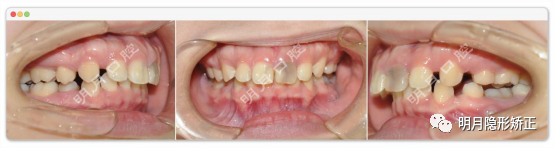

另一個案例,朋友的女兒在外地做了一年的矯正,因為各種原因要回來,希望我繼續幫她完成餘下的治療。

(圖為初診面照)

我給她拍了頭側位片,發現下頜后縮,低角,上前牙已經舌傾。但是:1、上頜還有很大的拔牙間隙沒關完,如果繼續內收上前牙,上前牙會更加舌傾,笑起來露出很多牙槽骨,如果不內收,拔牙間隙又怎麼辦?;2、上下前牙還是深覆合深覆蓋,如果繼續內收下前牙,將繼續加重這種情況,如果不內收,下頜的拔牙間隙又怎麼辦?